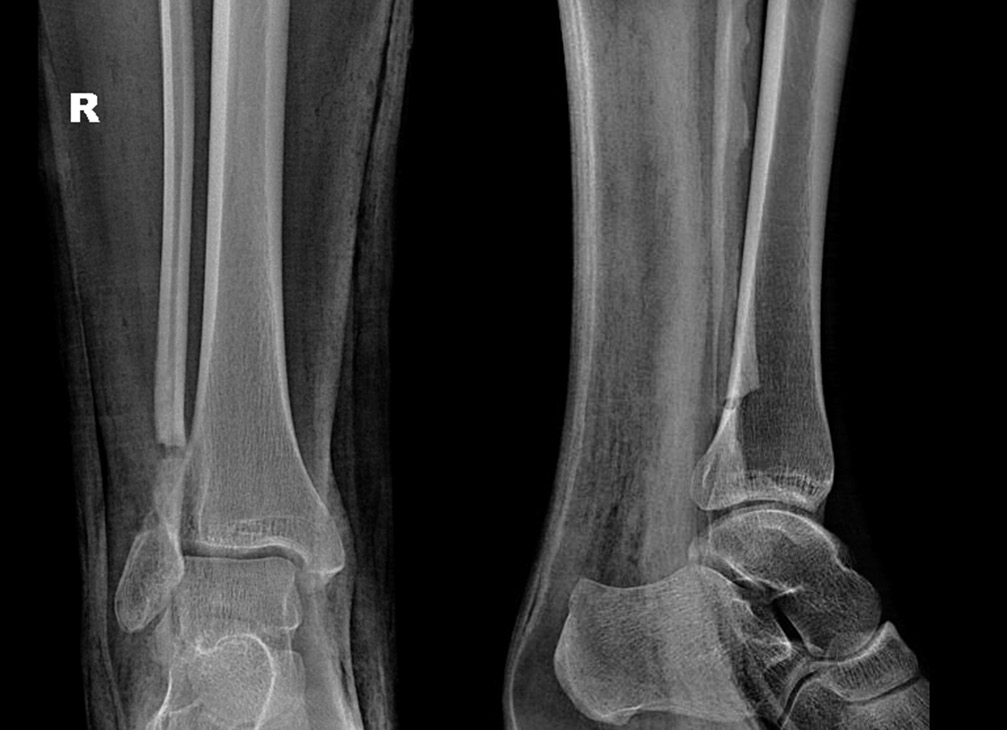

Ходьба при помощи костылей с дозированной нагрузкой на оперированную нижнюю конечность разрешена на 14-е сутки после оперативного вмешательства. На 21-е сутки после операции в зоне резекции костной кисты произошел перелом сохранившегося кортикального слоя малоберцовой кости без смещения (рис. 2). Иммобилизацию правой голени и стопы в постфрактурном периоде не осуществляли.

Рис. 2. Рентгенограмма. Состояние после оперативного лечения — краевой резекции пораженного отдела малоберцовой кости. Патологический перелом нижней трети малоберцовой кости, полость заполнена гранулами бета-трикальцийфосфата

Рис. 5. Рентгенограмма. Состояние через месяц после операции — сегментарной резекции склеротически измененного участка нижней трети малоберцовой кости